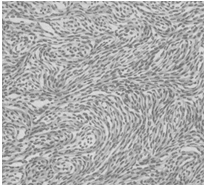

Опухоли матки

У немецкой овчарки в 1980 году в первый раз был описан наследственный синдром, который выражался в образовании множественных глубоких кожных узлов главным образом в области конечностей и в двусторонних кистах почек или раковых опухолях почек. Эта картина называется "генераизованный нодулярный дерматофиброз". Суки, страдающие этим заболеванием, дополнительно обнаруживают лейомиомы в матке (рис. 22, 23, 24).

рис. 24. Гистологический срез лейомиомы собаки.